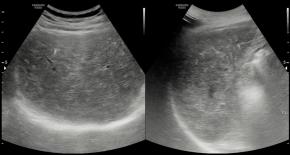

Elastography for the differential diagnosis of malignant versus benign testicular lesions: a meta-analysis

Ziwei Lin, Rui Lin, Huaiyu Wu, Linghu Wu, Jieying Zeng, Jinfeng Xu, Fajin Dong